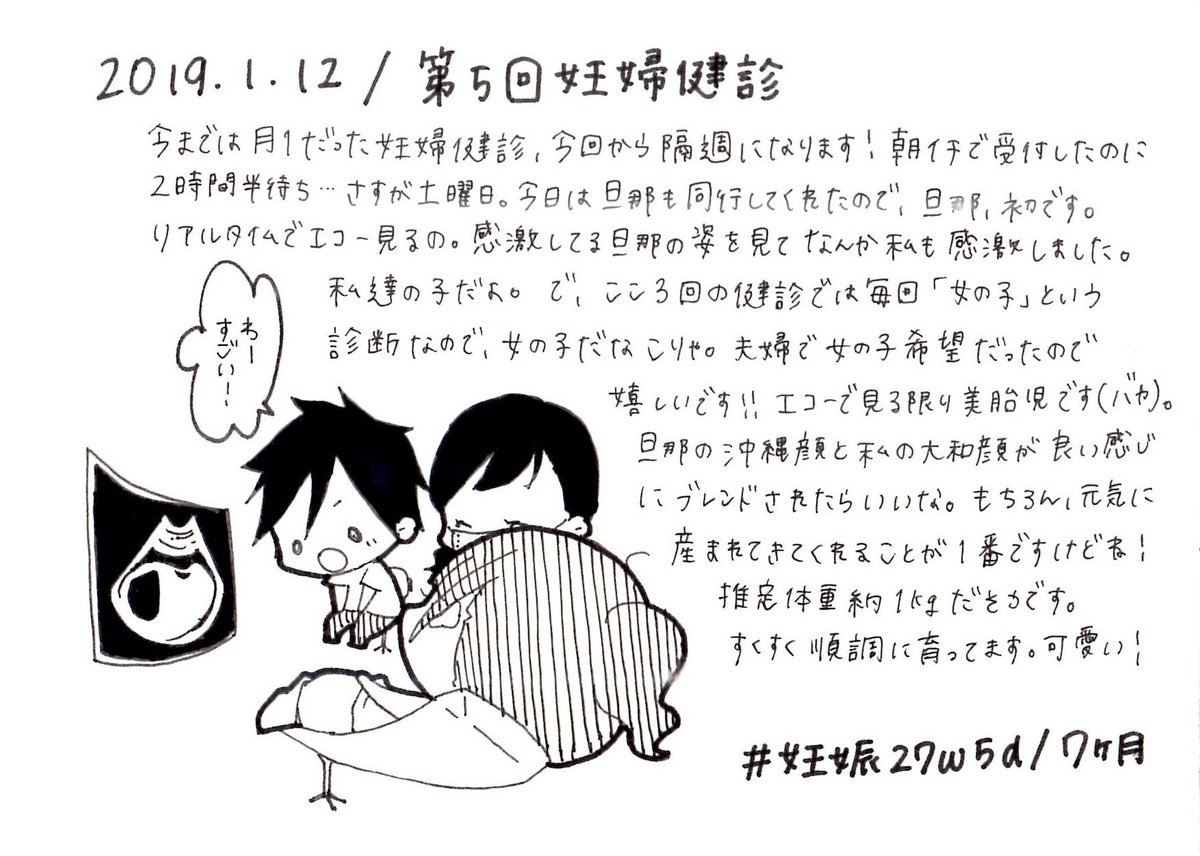

2019.1.12 第5回妊婦健診! 初めての旦那の同行。一緒にリアルタイムでエコー見られて嬉しかった! エコーとお腹の写真載せます、閲覧注意! #育児漫画 #育児日記 #妊娠 #妊娠中期 #妊婦健診 #妊娠7ヶ月 #ママ垢さんと繋がりたい #オリジナル漫画 #絵描きさんと繫がりたい pic.twitter.com/VJonZnb9wd